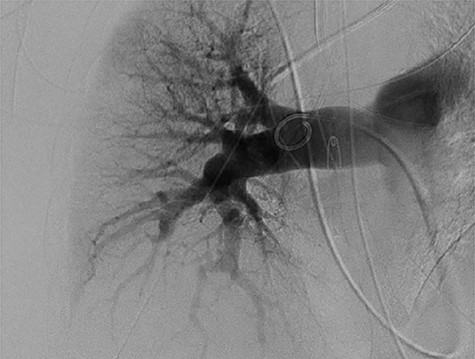

Upon arrival the patient underwent bronchoscopy and placement of an endobronchial blocker via endotracheal tube. Clotted blood was seen filling the right main-stem bronchus with the tail of the clot noted along the medial wall of the left main-stem bronchus. Neither clot was disturbed at that time. She then underwent a pulmonary angiogram to evaluate for a possible coiling procedure for a presumed pulmonary artery pseudoaneurysm. However, no pseudoaneurysm or aberrant vessels were demonstrated on angiography (Fig. 2).

Pulmonary arteriogram with no visualization of right pulmonary artery wall irregularity.